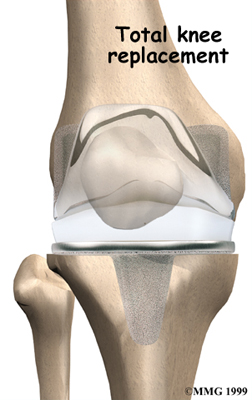

Artificial Knee Replacement

An artificial knee replacement is the ultimate solution for advanced knee OA.

Surgeons prefer not to put a new knee joint in patients younger than 60. This is because younger patients are generally more active and might put too much stress on the joint, causing it to loosen or even crack. A revision surgery to replace a damaged prosthesis is harder to do, has more possible complications, and is usually less successful than a first-time joint replacement surgery.

Related Document: FYZICAL Westminster's Guide to Artificial Joint Replacement of the Knee